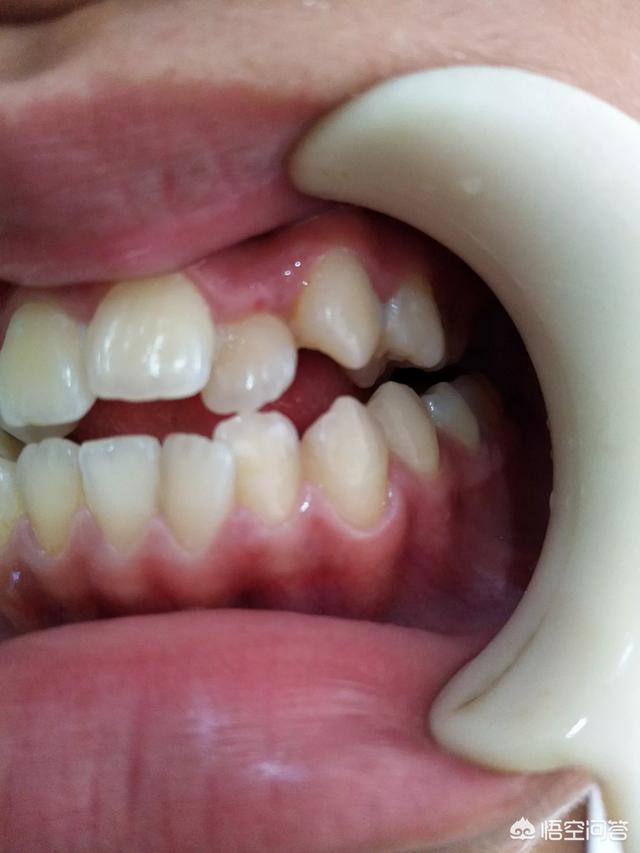

关于正畸不管你用传统方法还是最新的隐形矫正,想要达到矫正目的首先是要获取间隙(牙齿本身稀疏除外)。

而获取间隙的方法无外乎是减数(拔牙)、减径(片切牙缝)、扩弓(扩展狭窄的牙弓)此外还有推磨牙向后。

因为没有经过诊断,很抱歉这个问题无法给你提供建议和意见。如果描述能再详尽一些,并且附上牙齿咬合的照片也许才能帮到你。